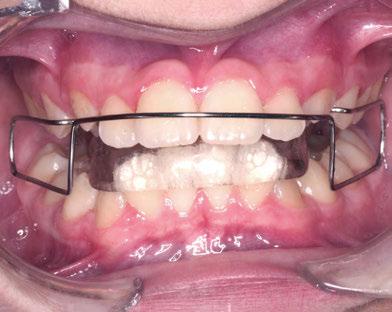

En este artículo se describe el caso de una niña de 9/2 años con síndrome de Clase II por hipoplasia mandibular que recibió tratamiento en dos fases: una primera, ortopédica, para estimular el crecimiento mandibular mediante aparatología funcional; y una segunda fase, ortodóncica, con la colocación de brackets de autoligado pasivo de la técnica USS (Universal Smile System) de prescripción variable para el desarrollo y coordinación de las arcadas dentarias.

Tras la terminación de la fase ortopédica, se continuó con la colocación de los brackets

mencionados anteriormente. La prescripción de estos fue de alto torque en los incisivos superiores y en los cuatro caninos, y de bajo en los incisivos inferiores. Tras 12 meses desde la colocación de los brackets y una vez conseguida la normalización de las relaciones oclusales, se colocaron unos retenedores fijos de canino a canino en ambas arcadas de acero trenzado de 6 hilos (.017” superior y .019” inferior) y un guarda de contención nocturna hasta la terminación del crecimiento puberal.

La exploración intraoral (figuras 4 a 8) revela una Clase II molar y canina completa, líneas 1/2 dentarias superior 0,5 mm e inferior 1 mm ambas desviadas hacia la derecha, los incisivos superiores excesivamente protruidos y vestibulizados (seguramente debido a la interposición del labio inferior), resalte de 13 mm y sobremordida 2/3 de corona. La discrepancia oseodentaria

inferior es de -3,5 mm y la curva de Spee de 4 mm.

Transcurridos 7 meses, se sustituyó por un Twin Block para un segundo y definitivo avance (figuras 12 a 16).

Este último aparato funcional se mantuvo en boca durante 8 meses, tras haber conseguido la mejoría esperada en cuanto al aspecto facial (figura 17) y las relaciones oclusales (figuras 18 a 22). La mordida abierta lateral producida es fácilmente solucionable en la siguiente fase de tratamiento.

Con el cementado de los brackets de la técnica Universal Smile System

(USS), como se aprecia en las figuras 23 a 25, comienza la segunda fase de tratamiento. Esta duró tan solo 12 meses debido a que gran parte de las relaciones oclusales habían mejorado durante la etapa anterior. Los resultados finales del tratamiento se observan en las figuras 26 a 30 , con la corrección de la clase molar y canina, el resalte y la sobremordida, el centrado de las líneas 1/2 y la curva de Spee. La mejoría en la macro, mini y microestética facial se aprecia en las figuras 31 a 33 , a pesar de la evidente desviación del mentón hacia

la derecha debida a la asimetría ósea detectada al inicio del tratamiento. En la figura 34 se muestran los cambios producidos por el tratamiento ortopédico-ortodóncico realizado, con la mejoría de casi todos los valores cefalométricos analizados, así como los ángulos de la convexidad (160 º), nasolabial (100 º) y mentolabial (118 º) más cercanos a la norma.